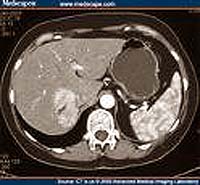

-  !important; Chụp CT scanner bụng có bơm thuốc tĩnh mạch cho thấy khối kích thước 6.0 × 5.0 × 4.0cm, nhiều vùng có tính chất hoại tử, không đồng nhất, giảm âm ở gan (P) lan rộng từ giữa ra ngoại vi, bờ và đến cả vỏ bao gan. Khối tổn thương này phân chia thành ngăn (septation) có xuất huyết nhu mô xung quanh.

Xem lại hình ảnh CT scan biểu hiện cùng các xét nghiệm trên, gợi ý là bệnh cảnh một nang nước (hydatid cyst) tồn tại bởi vì không có vỏ hoặc hình ảnh calci hóa, xuất hiện hình ảnh xuất huyết trong khoang. Chụp CT lại không thay đổi. Kết quả xét nghiệm huyết thanh cho amíp và Western blot cho Echinococcus đều (-), mẫu phân chứa Blastocystis hominis và Endolimax nana. Xét nghiệm huyết thanh với kháng thể Fasciola hepatica âm tính (FAST-ELISA);

Tuần tiếp theo, đếm eosin tăng lên 7.000/mm3 (46%) và dần dần giảm sau đó. Chụp cộng hưởng từ (MRI) cho thấy hình ảnh một u mạch hoặc u tuyến ở gan vỡ. Tuy nhiên, số lượng hồng cầu đã cho phép loại trừ. Test miễn dịch huỳnh quang gián tiếp (IIF_Indirect immunofluorescence ) kháng thể với Fasciola hepatica 1-2 tuần sau đó cũng âm tính với xét nghiệm FAST-ELISA, chỉ có hiệu giá kháng thể tăng lên 1:80 và 1:160 (1:20 là giới hạn ngưỡng [+]). Kết quả của điện di miễn dịch cũng dương tính, cho thấy 3 dải băng trên mẫu huyết thanh thứ nhất và 4 băng trên dải huyết thanh thứ 2. Bệnh nhân được điều trị bẳng thuốc đặc hiệu triclabendazole, liều duy nhất (10 mg/kg, 700mg), biệt dược Fasinex của hãng Novartis, Basel, Switzerland). Một kết quả chẩn đoánCT-scan 12 tuần sau đó cho thấy hầu như tổn thương đã được giải quyết hoàn toàn. Xét nghiệm phân cũng âm tính với F. hepatica ở tuần thứ 16. Triệu chứng của bệnh nhân không tái phát và đếm bạch cầu eosin cũng như xét nghiệm cận lâm sàng khác đều trở về bình thường. Một năm sau kiểm tra lại tất cả đều bình thường cả lâm sàng, cận lâm sàng và chẩn đoán hình ảnh.